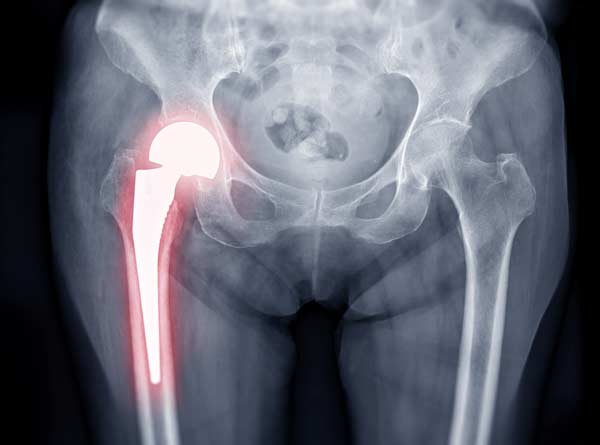

exactech implantExactech trató de ahorrar dinero en el empaque del producto. El aire oxida (degrada) los revestimientos de polietileno de los implantes de Exactech. Este revestimiento, que es exclusivo de estos implantes, es básicamente cartílago artificial. El fabricante lo llama amortiguador. Esta absorción de impacto ayuda a que estos dispositivos duren mucho más que los implantes metálicos. Entonces, el revestimiento es más que cosmético. Si falla un inserto, falla el reemplazo de la articulación.

Ya en agosto de 2021, Exactech les dijo a algunos médicos que "algunos" de sus implantes estaban empaquetados en bolsas de vacío defectuosas que "carecían de una capa de barrera de oxígeno adicional". Como resultado, cuando los médicos colocaron estos dispositivos en el cuerpo de sus pacientes, los dispositivos ya estaban peligrosamente defectuosos.

Sin el acolchado protector, los implantes articulares esencialmente se desmoronan debido al desgaste excesivo. El polietileno no es tan tóxico como otros tipos de plástico, principalmente porque no contiene BPD. Sin embargo, todavía es tóxico en algunos casos. Los desechos del propio implante podrían causar problemas similares de envenenamiento de la sangre.

A medida que el dispositivo se deteriora y el tejido circundante se inflama e infecta, los dispositivos migran fuera de sus lugares designados. Al principio, la incomodidad del paciente no es tan mala.

Muy rápidamente, el dolor se vuelve debilitante y la mayoría de las personas pierden la movilidad que habían ganado y se hace necesaria una cirugía de revisión.

Un médico debe abrir el cuerpo del paciente y extraer el implante. Dado que este implante ahora está en pedazos en todo el cuerpo, esta cirugía es larga y difícil. Luego, si el paciente quiere otra articulación artificial, el médico debe reemplazarla minuciosamente sin dañar más el tejido circundante que ya está débil.